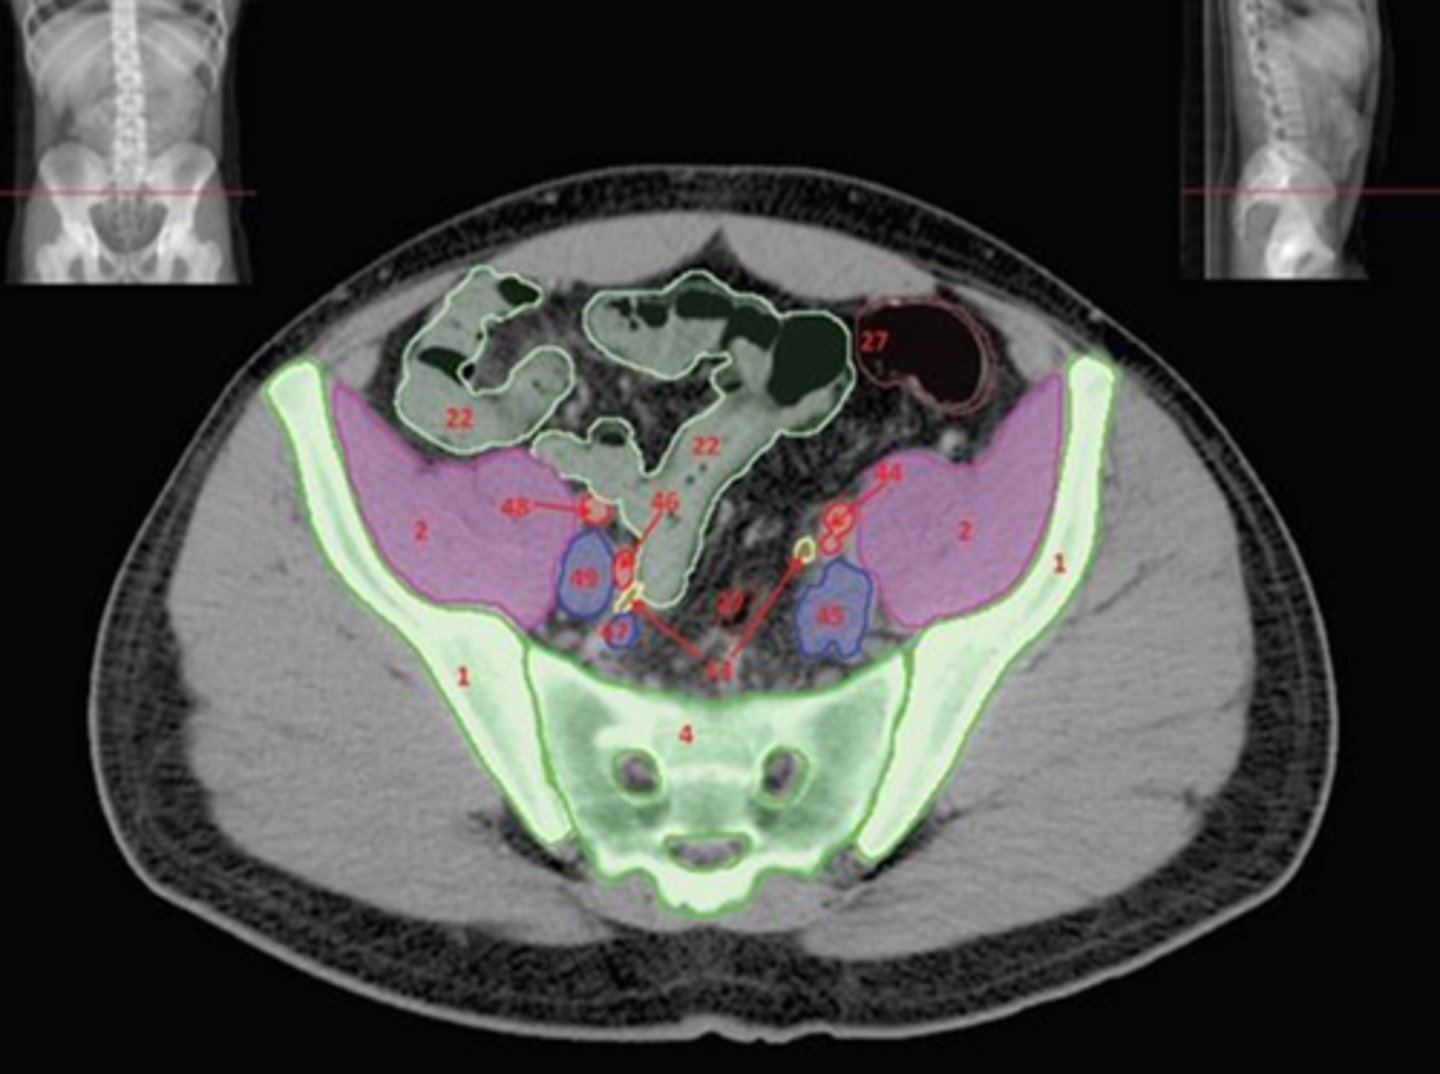

Name all numbered structures

1) L5

2) Sacrum

3) Conus medullaris

4) Cauda equina

5) Subarachnoid space with contrast

Name all numbered structures

1) SI joint

2) Body

3) Sacral promontory

4) Sacral canal

5) Ilium

6) Lateral mass

7) Articular process

Name all numbered structures

1) Ala of ilium

2) SI joint

3) Sacral promontory

4) Lateral mass of Sacrum

5) Sacrum

Name all numbered structures